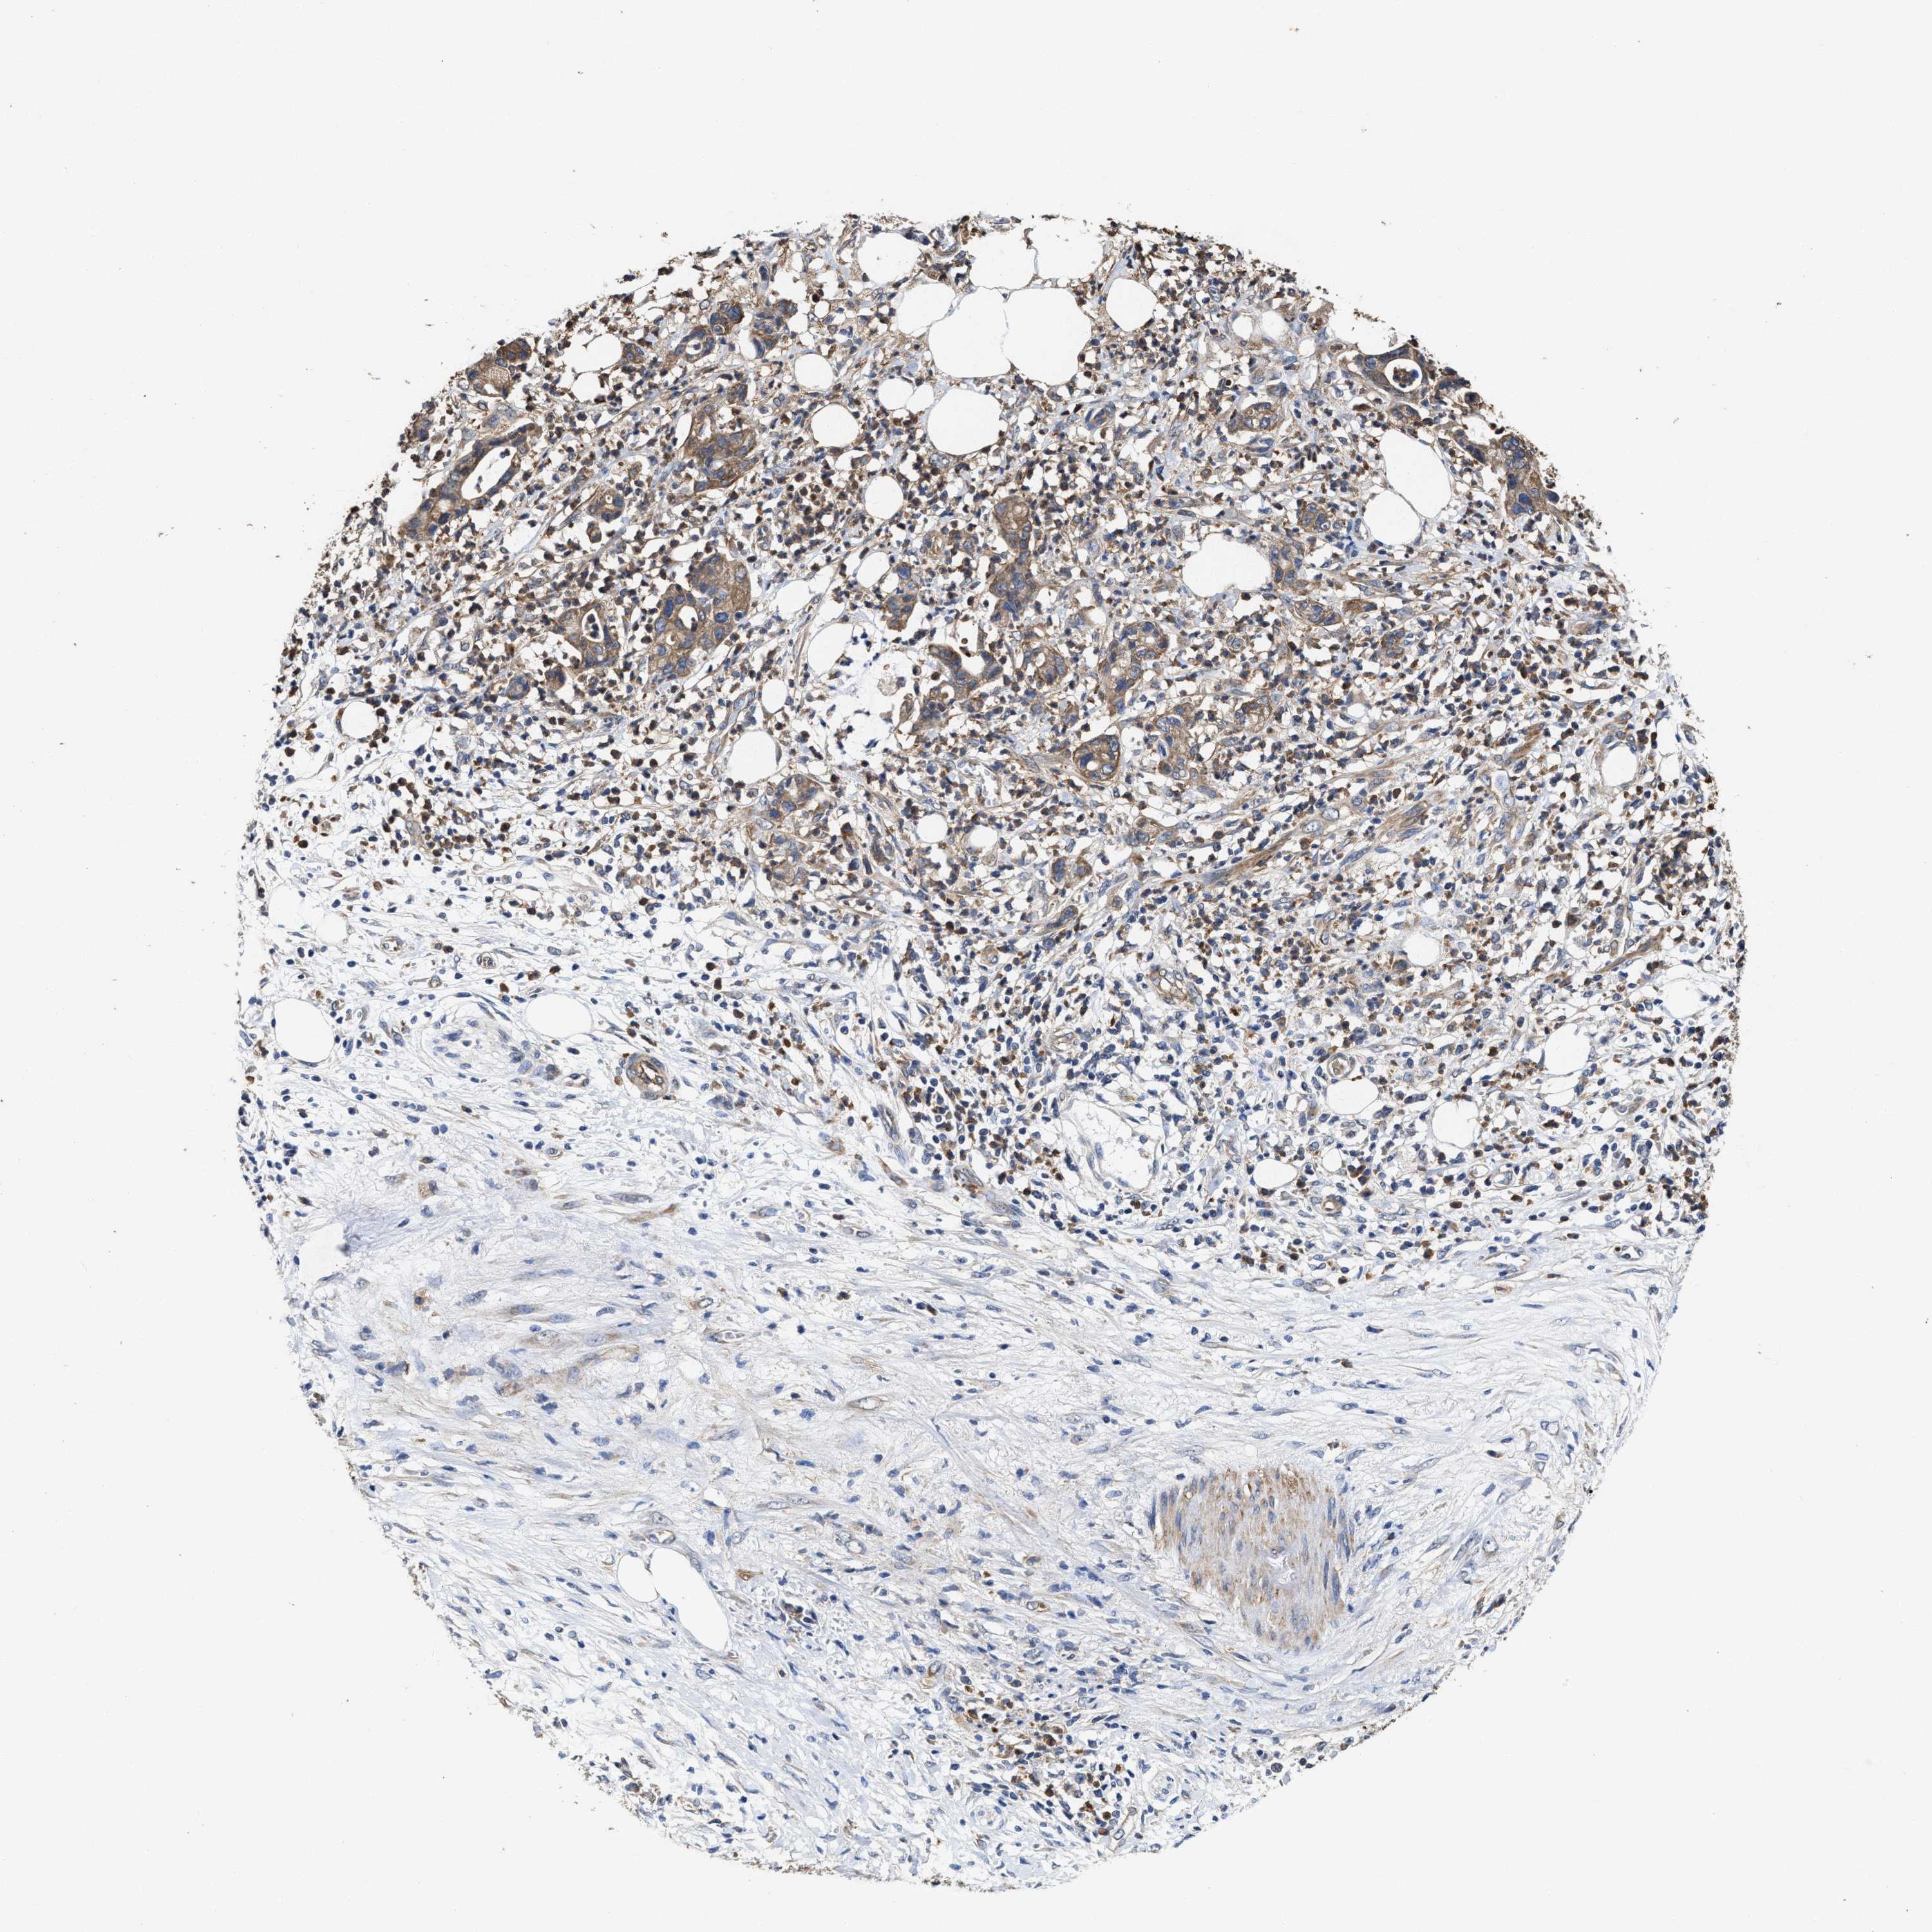

PANCREATIC CANCER - Protein expressioni

A mouse-over function shows sample information and annotation data. Click on an image to view it in a full screen mode. Samples can be filtered based on level of antibody staining by selecting one or several of the following categories: high, medium, low and not detected. The assay and annotation is described here.

Note that samples used for immunohistochemistry by the Human Protein Atlas do not correspond to samples in the TCGA dataset.

Antibody stainingi

Antibody staining in the annotated cell types in the current human tissue is reported as not detected, low, medium, or high, based on conventional immunohistochemistry profiling in selected tissues. This score is based on the combination of the staining intensity and fraction of stained cells.

Each image is clickable and will lead to virtual microscopy that enables deeper exploration of all samples and also displays staining intensity scores, fraction scores and subcellular localization as well as patient and tissue information for each sample.

Antibody HPA020872

Staining

High

Medium

Low

Not detected

Intensity

Strong

Moderate

Weak

Negative

Quantity

>75%

75%-25%

<25%

None

Location

Nuclear

Cytoplasmic/membranous

Cytoplasmic/membranous,nuclear

Adenocarcinoma, NOS